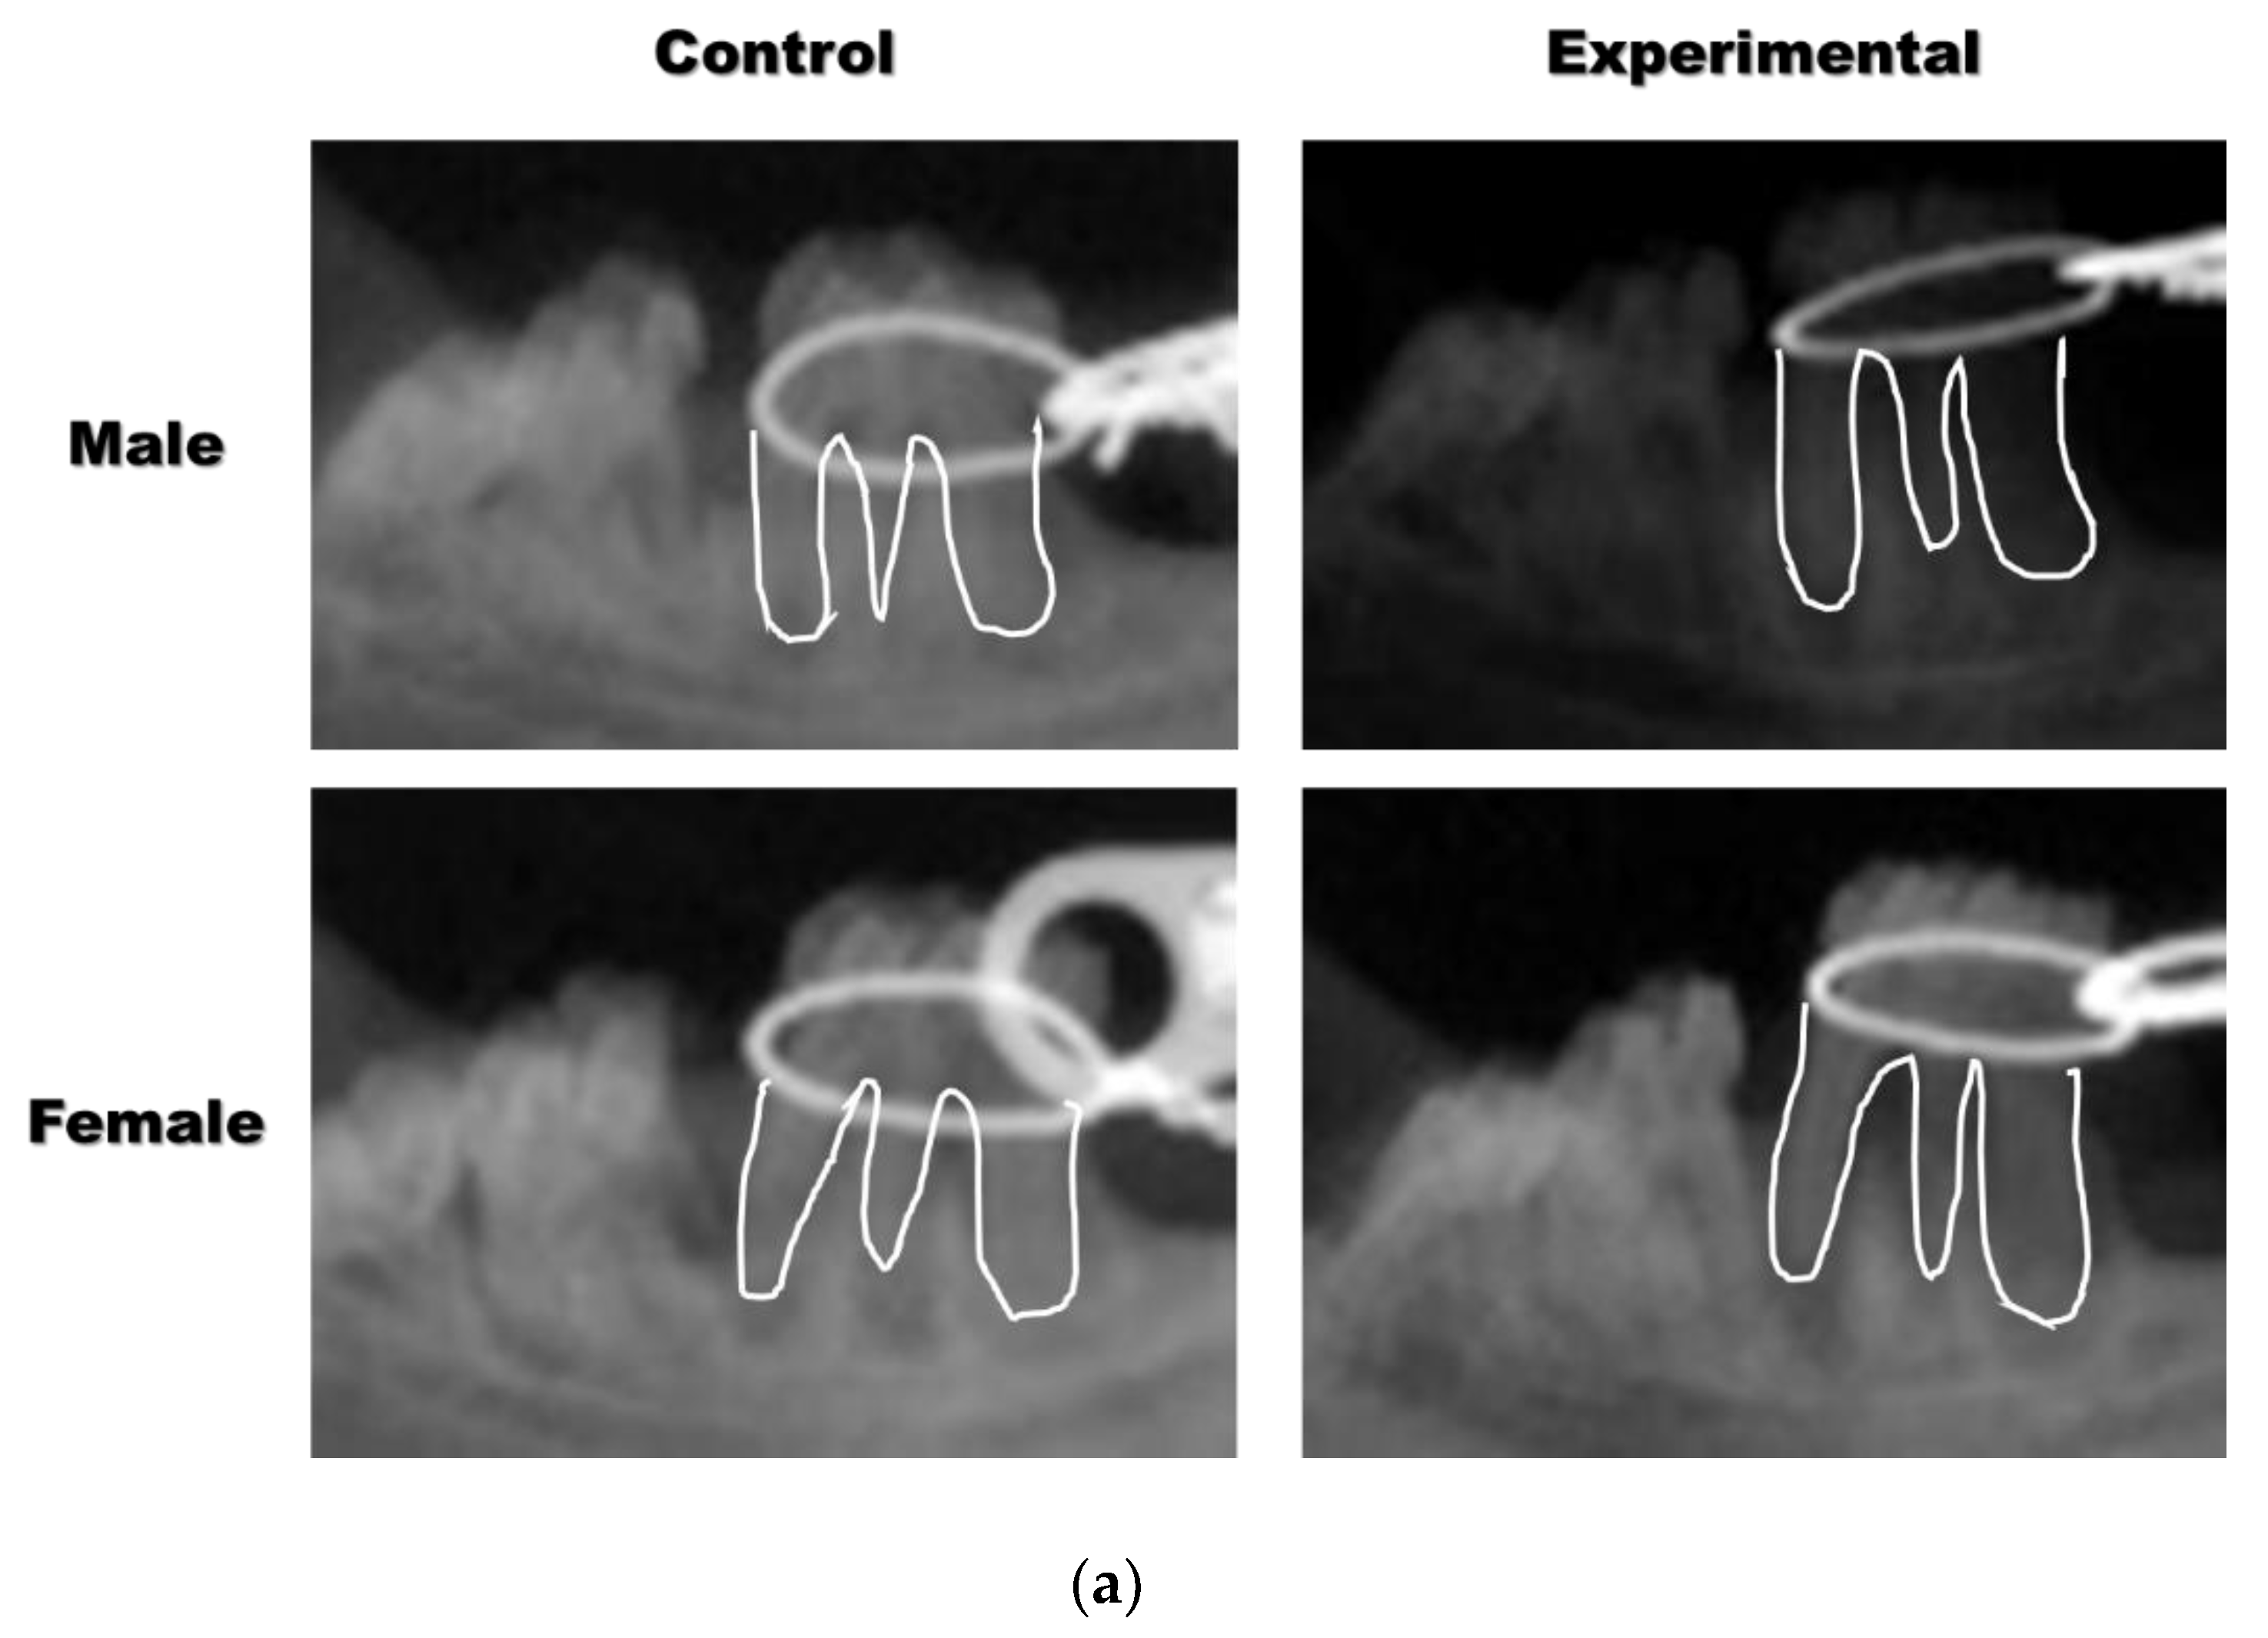

2.2. Plain X-ray and Micro-Computerized Tomography (mCT)

3.1. The Application of 4HR Inhibited Root Resorption during OTM